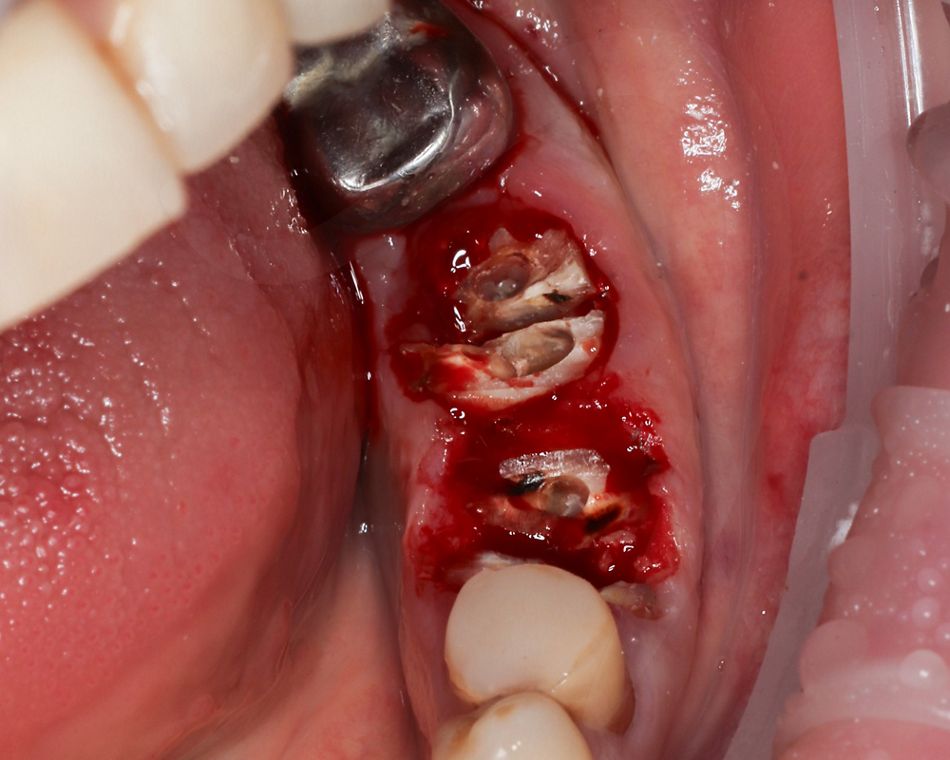

Поскольку сохранение альвеолярной кости имеет решающее значение для успеха немедленной имплантации, перед извлечением корней между ними подготовили фрезами ложа под имплантаты, чтобы избежать деформации кости на пути бурения, а затем с особой осторожностью удалили корни (Илл. 2).

Стенки лунки сохранили нетронутыми и тщательно освободили от грануляционной ткани, промыли стерильным раствором.

Иллюстрация 2

Модульную кассету Straumann® использовали для подготовки имплантационного ложа (Илл. 3).